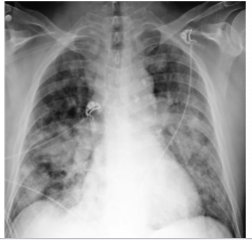

what is this?

lobar pna

multifactorial pna